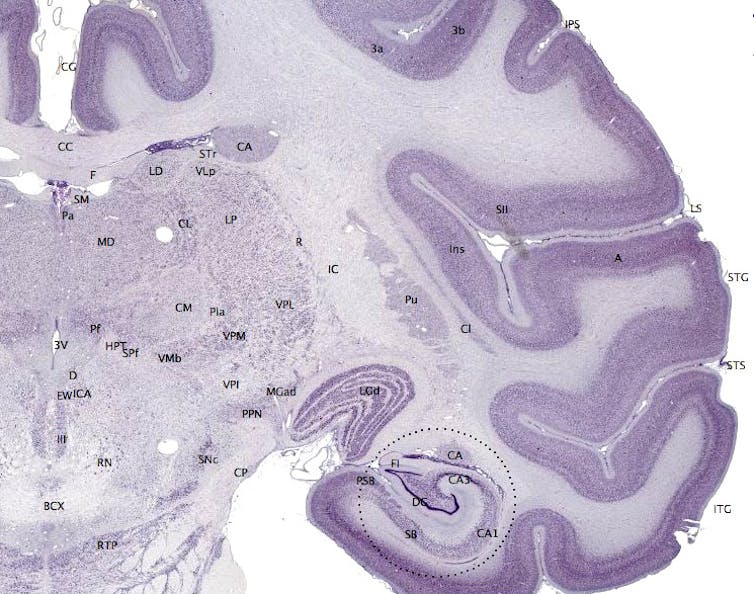

Eso es especialmente cierto en el giro dentado del hipocampo, a pesar de que hay otras regiones cerebrales que también producen nuevas células cerebrales.

Recientemente, un equipo de investigación de la Universidad de Harvard, liderado por Rudolph Tanzi, ha encontrado que el hipocampo puede producir entre 700 y 1 500 nuevas neuronas cada día. Quizás esto pueda no parecer mucho si tenemos en cuenta la vasta galaxia de neuronas que poseemos, pero incluso este pequeño número tiene valor, ya que mantiene activas muchas conexiones neurales ya existentes.

Así, si bien la mayoría de los cerebros puede desarrollar nuevas células, el objetivo de la ciencia ahora es encontrar las mejores maneras de hacerlo. La idea sería que, si se puede aumentar el número de neuronas aún más a través de la neurogénesis, se podría intensificar la función principal del hipocampo y mejorar la forma en que las personas aprenden nueva información y acceden a la memoria a corto y largo plazo.